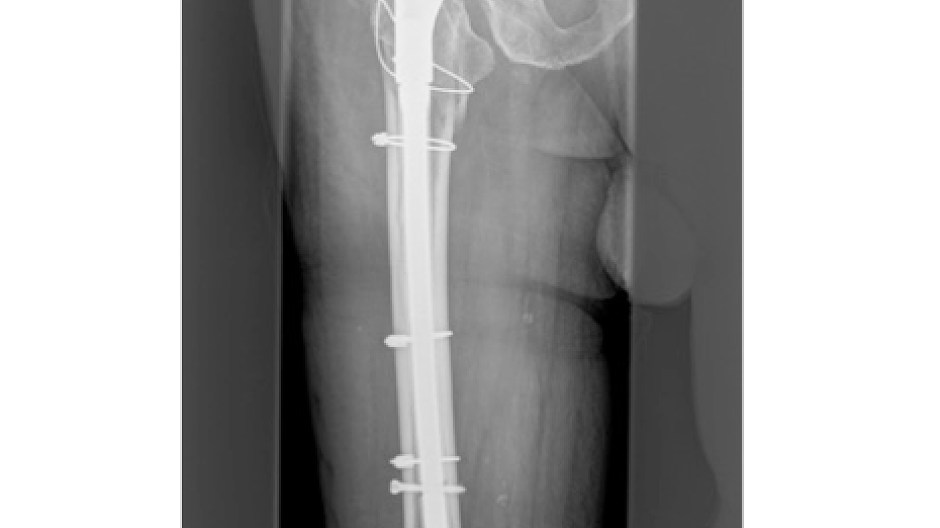

Fotos Unfallchirurgie und Orthopädie